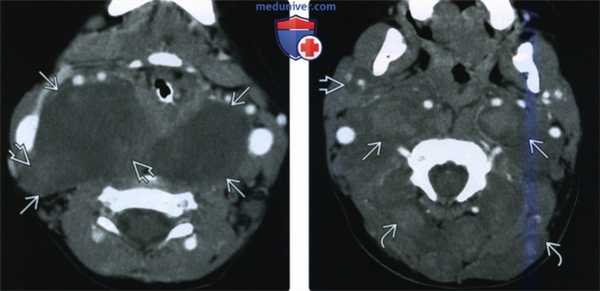

(Слева) При аксиальной КТ с КУ у ребенка с НФ1 визуализируются большие нейрофибромы сонного пространства типичного вида: низкой плотности с легким «пятнистым» контрастным усилением.

(Справа) При аксиальной КТ с КУ у ребенка с НФ 1 визуализируется массивная опухоль: многочисленные нейрофибромы в сонном пространстве с обеих сторон, околоушном пространстве справа, задних шейных пространствах. «Пятнистое» накопление контраста в центре с периферическим гиподенсным «ободком» встречается нередко.